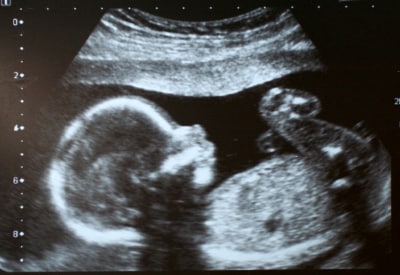

Figure 8: Ultrasound 2D image using 85 db pulses.

Ultrasound is effectively a high-frequency sonar system, measuring the minute echoes of sound waves as they pass through the body. Ultrasound images (see Figure 8) resemble x-rays except that they are displayed in real-time.